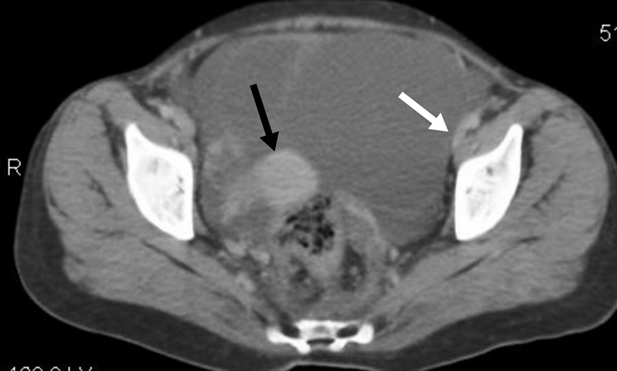

observed on abdominal ultrasonography (us). Computed tomography (ct) showed a

large well-defined heterogeneous cystic mass lesion with irregular lobulated

margins, measuring approximately 10 x 11 cm, which is noted in the left adnexa.

The lesion appears to arise from the left ovary. It had a small solid

peripheral enhancing component and a large internal non-enhancing necrotic

area. It had thin enhancing walls with few septations. The lesions have a

distinct interface with the surrounding structures and do not invade the gut

loops or pelvic walls. Posteriorly, the lesion did not extend to the pelvic

sidewall or rectum. Superiorly, the lesion extended into the lower abdomen with

the displacement of the bowel in the region. There was no evidence of

calcification or haemorrhage within or adjacent to the lesion. Another large

heterogeneous enhancing lesion was seen in the right adnexa measuring 5.3 x 3

cm. The right ovary was visualized separately from the lesion shown in (figure 1).

Figure 1. Black arrow shows right ovarian

lesion. White arrow shows peritoneal involvement.